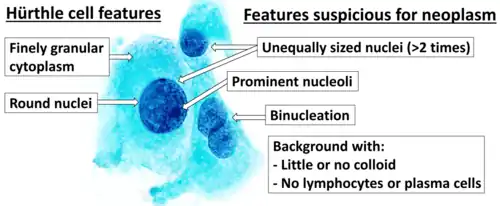

Category V with nuclear groove (arrow) Cytopathology suspicious for Hürthle cell neoplasm (Bethesda category IV, rather than Hürthle cell hyperplasia), Pap stain.[14]

Cytopathology suspicious for Hürthle cell neoplasm (Bethesda category IV, rather than Hürthle cell hyperplasia), Pap stain.[14]

- ↑ Image by Mikael Häggström, MD. References for findings:

- Ayana Suzuki, C.T., Andrey Bychkov, M.D., Ph.D. "Hürthle cell neoplasm". Pathology Outlines.{{cite web}}: CS1 maint: multiple names: authors list (link) Last author update: 7 May 2020. Last staff update: 12 May 2022

- Shawky M, Sakr M (2016). "Hurthle Cell Lesion: Controversies, Challenges, and Debates". Indian J Surg. 78 (1): 41–8. doi:10.1007/s12262-015-1381-x. PMC 4848220. PMID 27186039. - ↑ Renuka, I.V; Saila Bala, G; Aparna, C; Kumari, R; Sumalatha, K (December 2012). "The Bethesda System for Reporting Thyroid Cytopathology: Interpretation and Guidelines in Surgical Treatment". Indian J Otolaryngol Head Neck Surg. 64 (4): 305–311. doi:10.1007/s12070-011-0289-4. PMC 3477437. PMID 24294568.